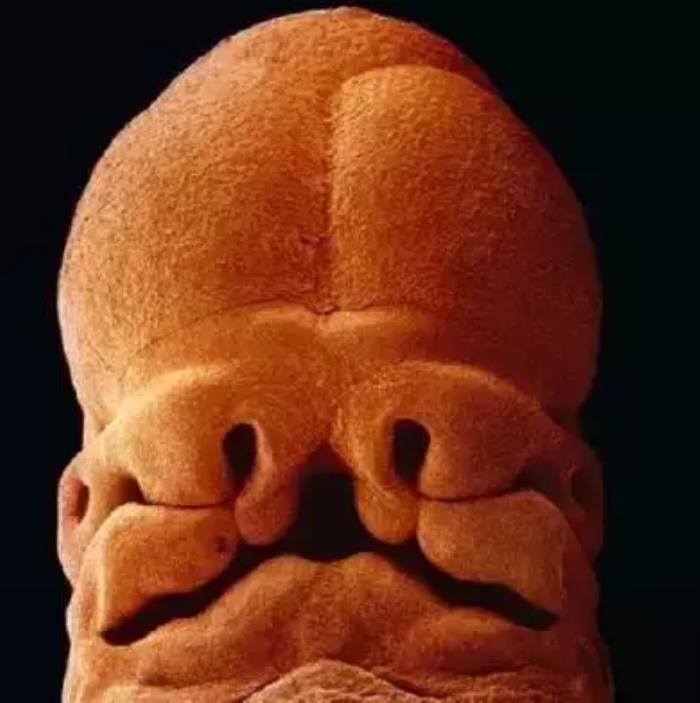

5周大的胎儿。此时胎儿只有大约9毫米长,面部正在发育,嘴巴、鼻孔和眼睛正在形成

第10周。此时眼睑半闭,几周内会完全闭合

10周。胎儿已经可以使用双手来探索周围的环境